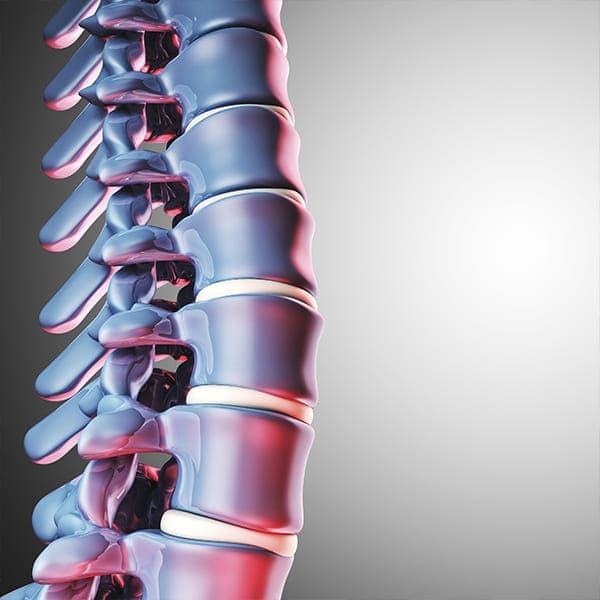

Descompresión Nerviosa

Ampliación Convencional de Conducto Lumbar Estrecho

Cirugía para ensanchar el espacio dentro de la columna y aliviar la presión sobre los nervios.

Recalibraje de Conducto Lumbar Estrecho

Corrige estrechamientos en la columna, utilizando técnicas que preservan la integridad de la estructura vertebral.